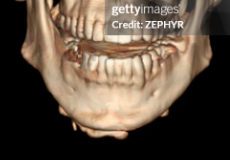

finger used as guide to where ramus ends

finger used as guide to where ramus ends